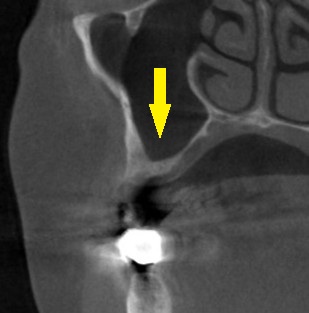

これならと同意いただけましたので、本日、直径6mm、長さ7mmのインプラントを人工骨を用いることなく埋入しました。

下の写真、2段目が手術前、3段目が手術後のCTです。